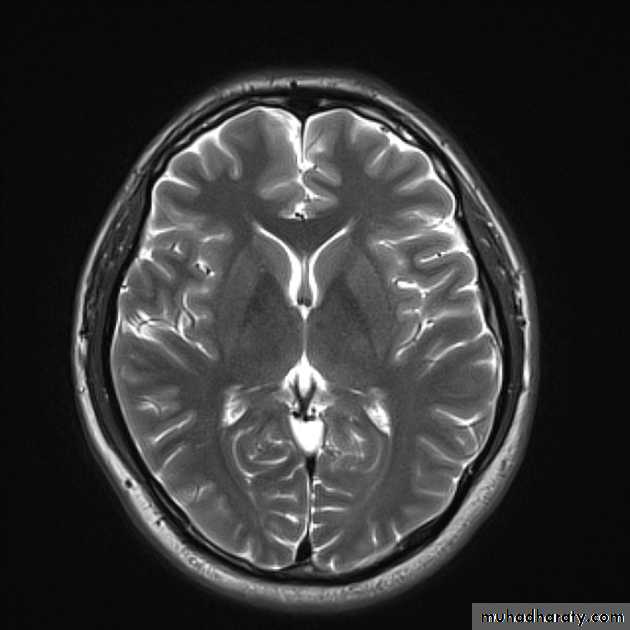

• Superolateral surface

• 1. Lateral sulcus:

• Insula• Central Sulcus

• 4. Frontal gyri:

• 5. Temporal Gyrus:

• 5. Parietal lobe :

• 6. Occipital lobe: